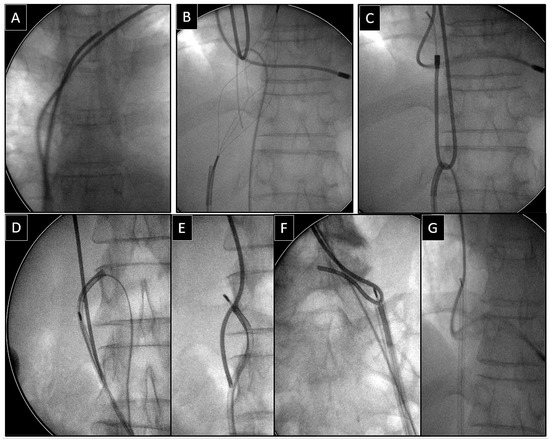

Extraction of Leads with Migrated Proximal Ends into the Cardiovascular Space